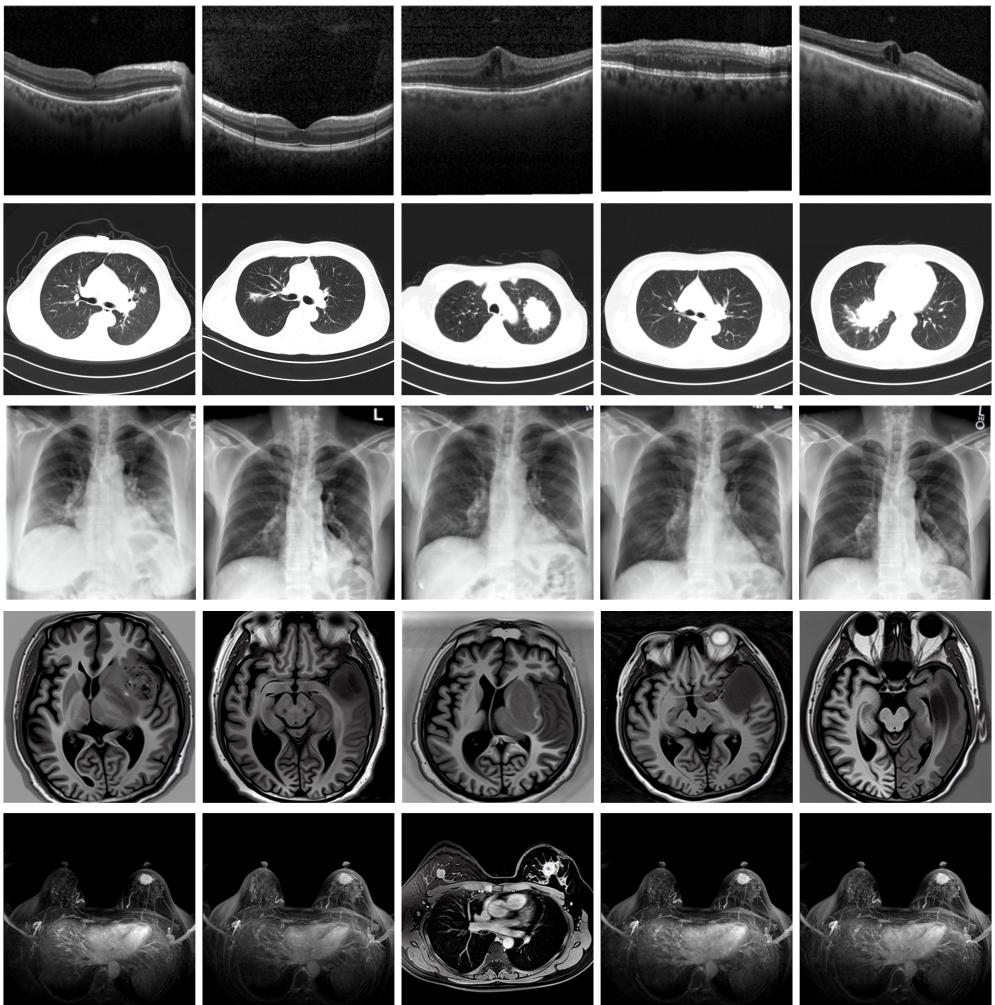

圖為由MINIM生成的高質(zhì)量醫(yī)學合成圖像(受訪者供圖)

“目前公開的醫(yī)學影像數(shù)據(jù)非常有限,我們建立的生成式模型有望解決訓練數(shù)據(jù)不夠的問題?!北本┐髮W未來技術(shù)學院助理研究員王勁卓說,研究團隊利用多種器官在CT、X光、磁共振等不同成像方式下的高質(zhì)量影像文本配對數(shù)據(jù)進行訓練,最終生成海量的醫(yī)學合成影像,其在圖像特征、細節(jié)呈現(xiàn)等多方面都與真實醫(yī)學圖像高度一致。

實驗結(jié)果顯示,MINIM生成的合成數(shù)據(jù)在醫(yī)生主觀評測指標和多項客觀檢驗標準方面達國際領(lǐng)先水平,在臨床應(yīng)用中具有重要參考價值。在真實數(shù)據(jù)基礎(chǔ)上,使用20倍合成數(shù)據(jù)在眼科、胸科、腦科和乳腺科的多個醫(yī)學任務(wù)準確率平均可提升12%至17%。